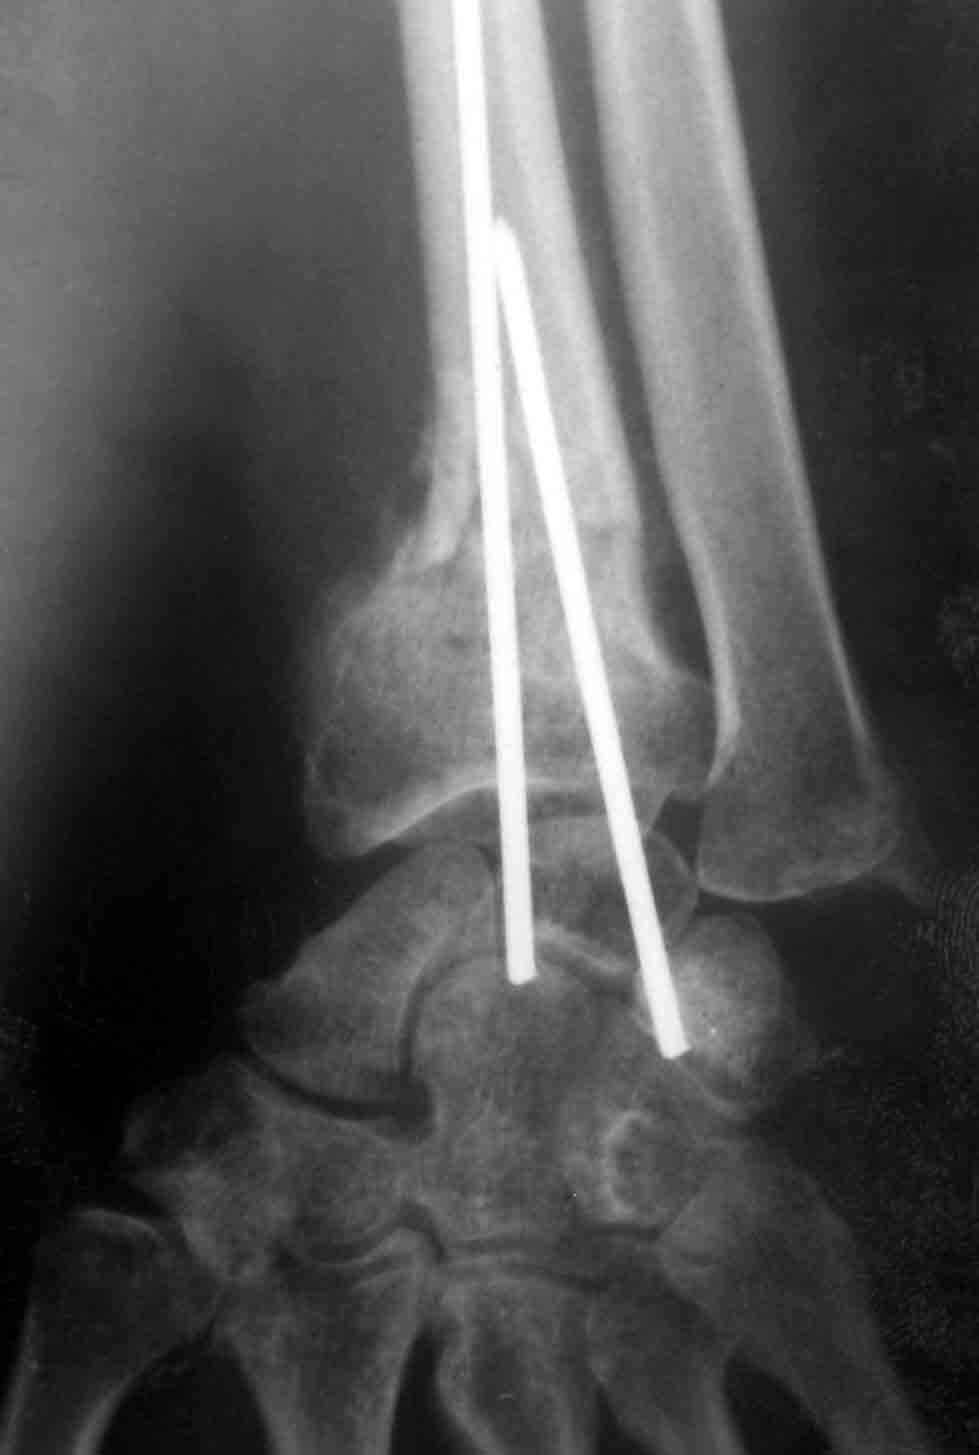

Травматическая деформация предплечья

После 4 месячного лечения в поликлиниках города 43 летняя пациентка, экономист поступила с грубой деформацией правого предплечья, контрактурой пальцев и невритом срединного нерва средней степени тяжести. После неплохой репозиции чрезсуставного трехфрагментарного перелома луча месяц провела в гипсе без рентгенконтроля. После снятия повязки ввиду лучевой девиации была предпринята какая-то остеотомия без костной пластики, деформация лишь усугубилась, головка локтя в вывихе.

Учитывая молодой возраст в моих планах укорачивающая остеотомия локтевой кости, корригирующая остеотомия луча( перелом там похоже не сросся)для восстановления угловых соотношений в суставе с заполнением дефекта кости материалом из локтевой и коллапаном. Локтевая подлежит фиксации АО пластиной, лучевая, скорее всего, обойдется без фиксации. В моей практике ранее были остеотомии луча, удаления головки локтевой кости у престарелых, но укорачивающих остеотомий не производил. Кто имеет опыт подобных операций, поделитесь, понимаю, что необходим невролиз медиануса, но третий разрез в этой зоне не хочется выполнять. На англоязычных сайтах много материала по подобным случаям, на отечественных практически ничего